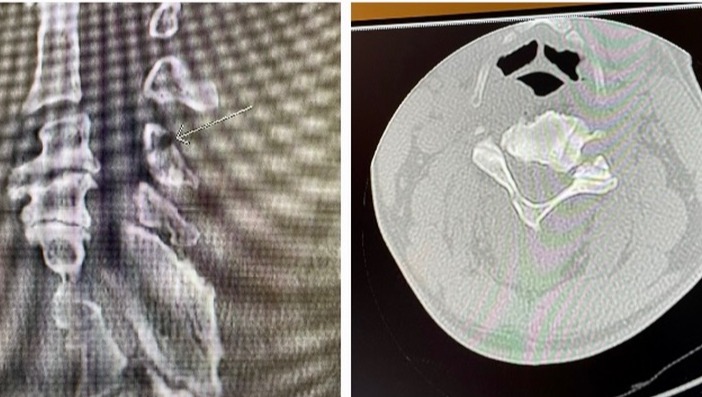

The man is a gentleman and does a ton for his two boys. He was injured surfing by someone dropping in and then losing his board and the board hitting him in the back of the neck. His neck was broken in 4 places and he will be unable to work for 3 months at the very least. He does so much for the surf scene on Kaua'i, is an ambassador of Aloha and needs our help to provide for his boys.

"Yesterday while surfing Hanalei a loose longboard hit me in the back of my head and broke my neck. I was helping an unko that had lost his board when it happened. The pain was indescribable. I thought I was done. I screamed in pain, held my neck with my left hand and paddled with my right arm. My whole life flashed in front of me and all I thought about was my Zboyz. I just kept going towards the beach, screaming for help n no one helped til I got to the shore. Luckily I knew a guy (I forget his name) carried me to the dry sand. I was lucky once again. People, please use a leash and stop hurting others in the lineup. From Pakalas to Hanalei, please think of others. The life you save may not be your own."